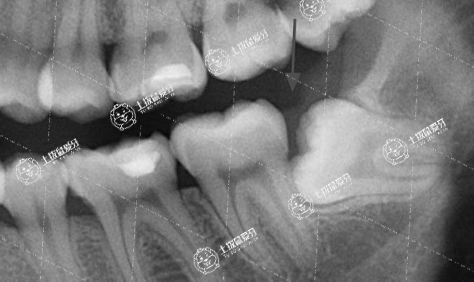

4、矯正結(jié)束后長(zhǎng)智齒

智齒不正常萌出

多數(shù)矯正病例,在治療前醫(yī)生會(huì)提出拔掉智齒。但是有些青少年在矯治時(shí)智齒還未萌出,于是后期長(zhǎng)出的智齒有可能會(huì)壓迫其它牙齒,而引起反彈發(fā)生。